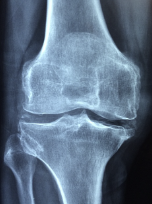

무릎 관절에 좋은 음식 무릎 관절 관리 방법 등 정보에 대해 알아보도록 하겠습니다. 무릎 관절은 우리 몸에서 가장 중요한 부위 중 하나입니다. 다리를 지탱하고, 움직임을 제공하는 기능을 수행합니다. 무릎 관절은 대개 체중과 운동에 의해 과부하가 걸리기 때문에, 연령과 상관없이 다양한 질환과 손상이 발생하기 쉽습니다. 무릎 관절 질환에는 퇴행성 관절염, 무릎 관절염, 슬관절 연골손상 등이 있습니다. 이러한 질환은 무릎 관절 통증, 붓기, 운동 제한 등의 증상을 유발합니다. 무릎 관절 건강을 유지하기 위해서는 적절한 운동, 올바른 식습관, 적절한 체중 유지, 적절한 자세 등이 필요합니다. 무릎 관절 질환의 예방과 관리를 위해서는 정기적인 건강 검진과 치료가 필요합니다.

무릎 관절염 증상

무릎 관절염의 증상은 다음과 같습니다.

- 통증: 무릎 관절염의 가장 일반적인 증상은 무릎 주변의 통증입니다. 특히, 오랫동안 앉거나 서 있거나 움직일 때 더 심해집니다.

- 뻣뻣함: 무릎 관절염은 무릎 관절의 뻣뻣함을 유발합니다. 무릎 관절의 움직임이 제한되며, 일어나거나 앉는 것이 어려울 수 있습니다.

- 부종: 무릎 관절염으로 인해 무릎 주변의 부종이 발생할 수 있습니다. 부종은 무릎 관절에 더 많은 압력을 가해 더 많은 통증을 유발합니다.

- 열감: 무릎 관절염은 관절 주위 조직의 염증으로 인해 무릎 주변에서 열감을 느낄 수 있습니다.

- 소리: 무릎 관절염은 무릎 관절에서 윤활제 분비 감소로 인해 뼈가 마찰되어 생기는 부적합한 소리를 유발할 수 있습니다.

무릎 관절염의 증상은 진행되는 정도에 따라 다양합니다. 초기에는 가벼운 통증이 있을 수 있으나, 진행되면서 무릎 관절의 기능 저하와 더 심한 통증이 발생할 수 있습니다. 무릎 관절염이 의심되면, 증상이 심화되기 전에 적극적인 치료와 예방 조치를 취하여 증상의 악화를 방지해야 합니다.